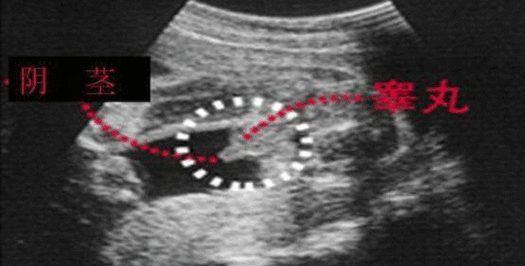

四维彩超胎儿睾丸图片

孕26周四维下睾丸的样子 如何看四维彩超识性别